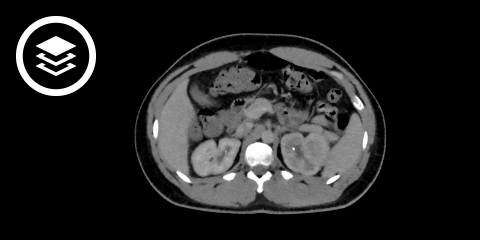

CT-Fallbeispiel

DICOM-Modelle können auf Mobilgeräten leider nicht angezeigt werden.

- Bildquelle DICOM-Viewer: Datensatz freundlicherweise zur Verfügung gestellt durch die Klinik für diagnostische und interventionelle Radiologie, St. Vinzenz Hospital Köln